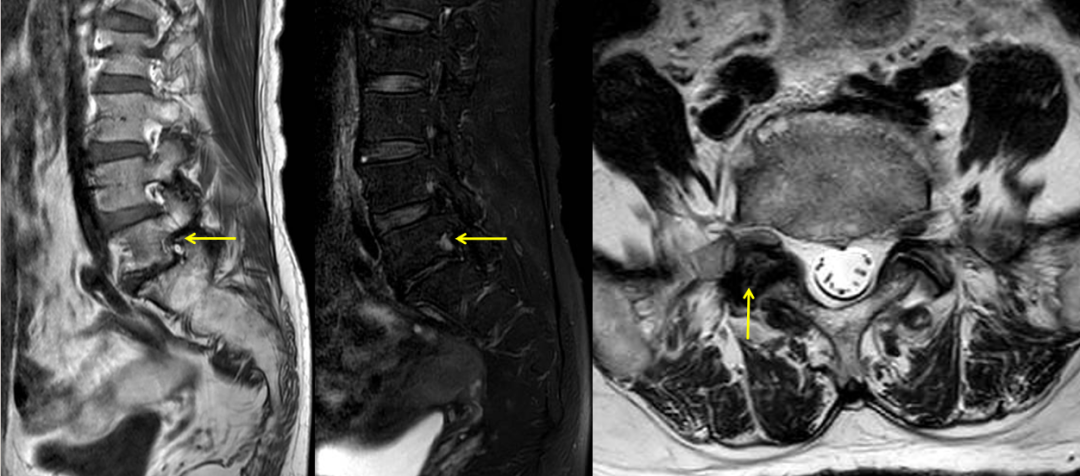

术前MR

接诊后,中山三院脊柱外科派驻中山三院粤东医院的专家刘仲宇主任指导团队为苏女士进行了系统评估。通过详细的病史询问、体格检查并结合影像学资料,刘主任敏锐发现其右下肢疼痛根源并非此前其他医院诊断的“腰椎间盘突出”、“肌肉劳损”或者“神经系统病变”,而很可能是由L5-S1右侧椎间孔狭窄导致的右侧L5神经根受压所引起。“椎间孔是神经根穿行的通道,当这个空间因骨质增生、韧带肥厚等原因变窄时,神经就会被卡住,引发剧烈疼痛。”刘主任解释道。

为了进一步明确诊断,团队为患者实施了选择性右侧L5神经根造影及封闭检查,在透视下将药物精准注射至疑似病变神经根周围,以达到暂时麻痹病变神经根的目的。注射药物前患者在手术室坐2分钟即出现右下肢疼痛难忍的情况,而注射后立即让患者再次尝试坐位7分钟后仍未出现右下肢不适。说明右侧L5神经根就是病变神经根,证实了诊疗团队的病因推测,明确了诊断。